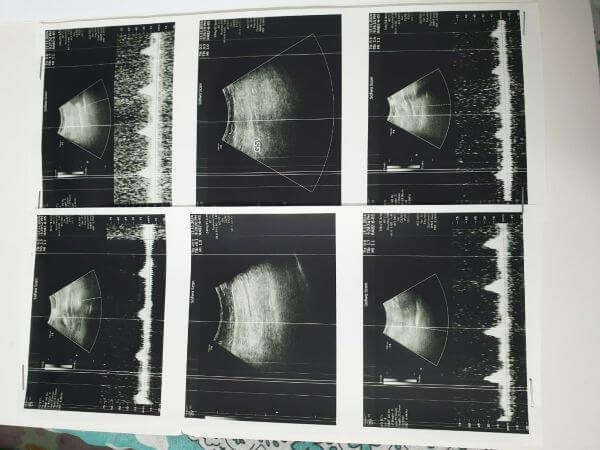

سلام المسيح أمنا ماغي أنا عبدلله داود داود مقيم في لبنان مريض ربو مزمن ومريض قلب وضغط اعاني من فترة من بحصة بالغدة اللعابية مسببة لي ألم مع ورم وصعوبة في البلع بعد الفحص طلب الحكيم اجراء عمل جراحي بأسرع وقت وانا ماعندي إمكانية مادية العملية بتكلف 1400 دولار بطلب منك المساعدة باسم الرب يسوع المسيح